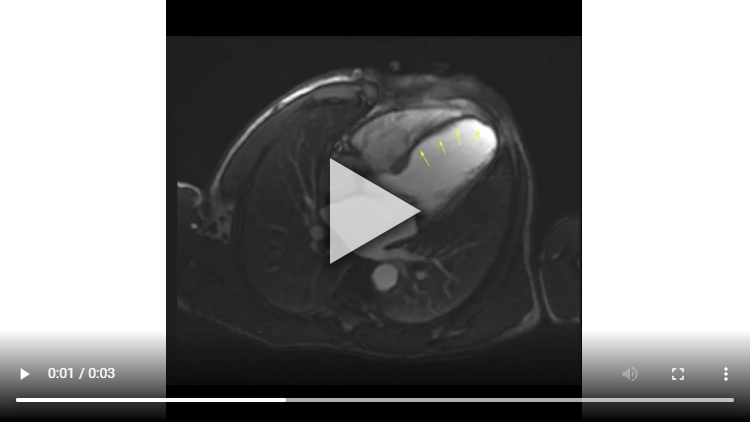

Figure 1A : Séquence Ciné-IRM - Coupes petit-axe médian

Présence d’un VG dilaté avec VTD VG mesuré à 119 ml/m2 associé à une large hypokinésie sévère, voire akinésie dans certains segments, de toute la paroi antéro-septo-apicale et débordant sur la paroi apico-latérale.

Altération de la FEVG mesurée à 33% après segmentation VG.

Aucun thrombus intra-VG n’est visualisé sur ces séquences de ciné-IRM.